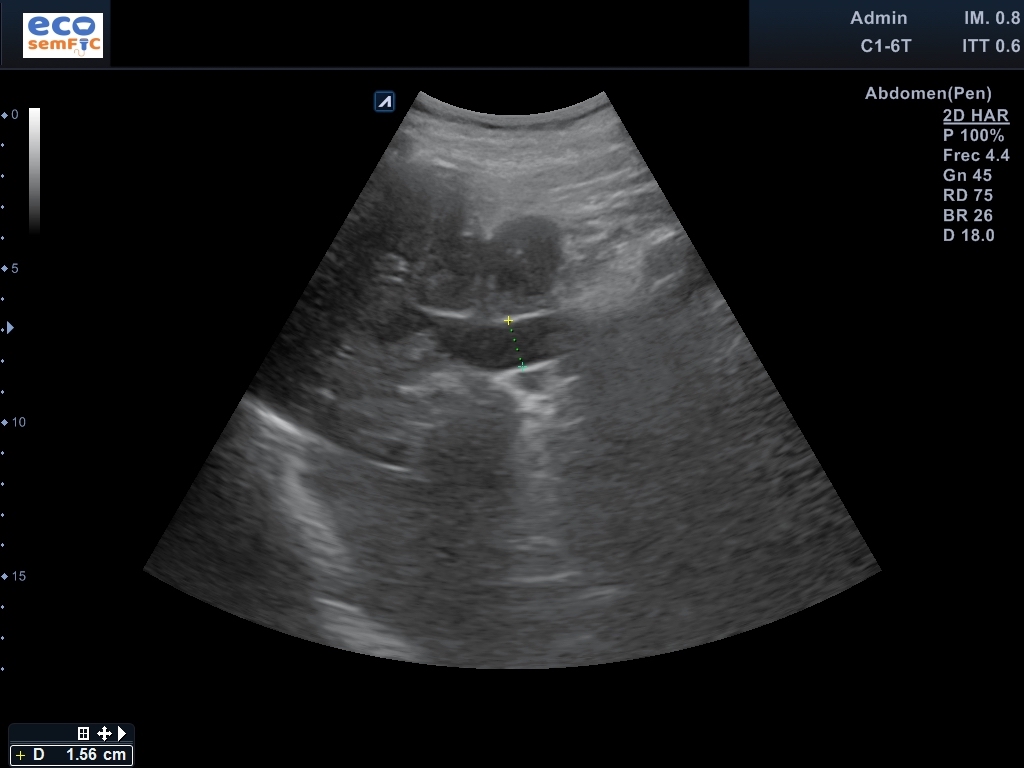

Limitada por poca colaboración, pero aceptable. En las áreas accesibles, hígado de superficie lisa y contorno regular, heterogéneo sin aparentes LOEs. Radicales intrahepáticos dependientes del conducto hepático derecho ectásicos. Colédoco proximal de 8,3 mm y distal de 14,3 mm a nivel de la cabeza del páncreas. Marco duodenal ocupado por contenido sólido aperistáltico en este momento. Páncreas visualizado en toda su extensión con Wirsung patente no dilatado, sin lesiones focales. Riñones de aspecto senil, conservan el grosor cortical y diferenciación parénquima-seno. Bazo homogéneo no aumentado ni lesiones parenquimatosas. Ausencia líquido libre o colecciones en áreas exploradas.